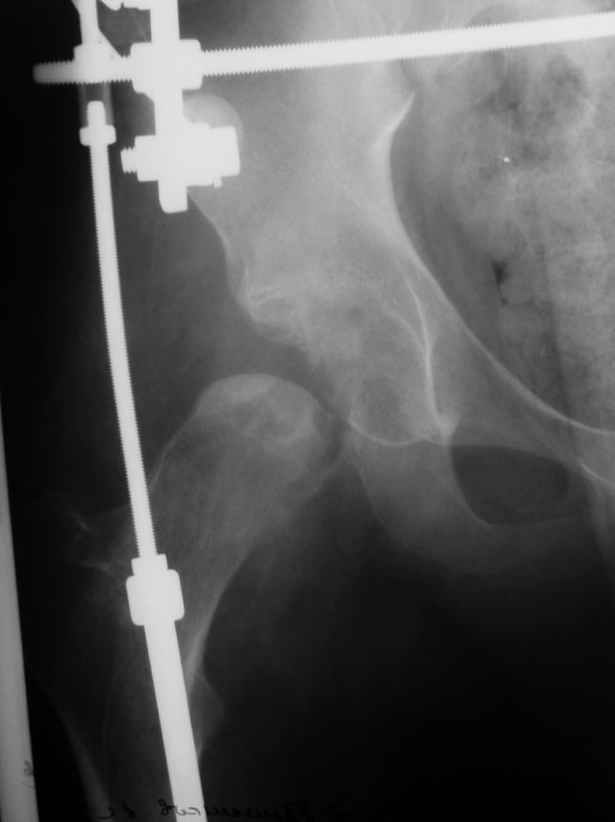

Уважаемые коллеги! Две недели назади мы прооперировали данного пациента: монтаж аппарата таз-бедро (с двусторонней фиксацией за крылья) и постепенная дистракция. Достигнуто низведение бедра.

планируется открытое вправление вывиха с удалением интерпонированных тканей.